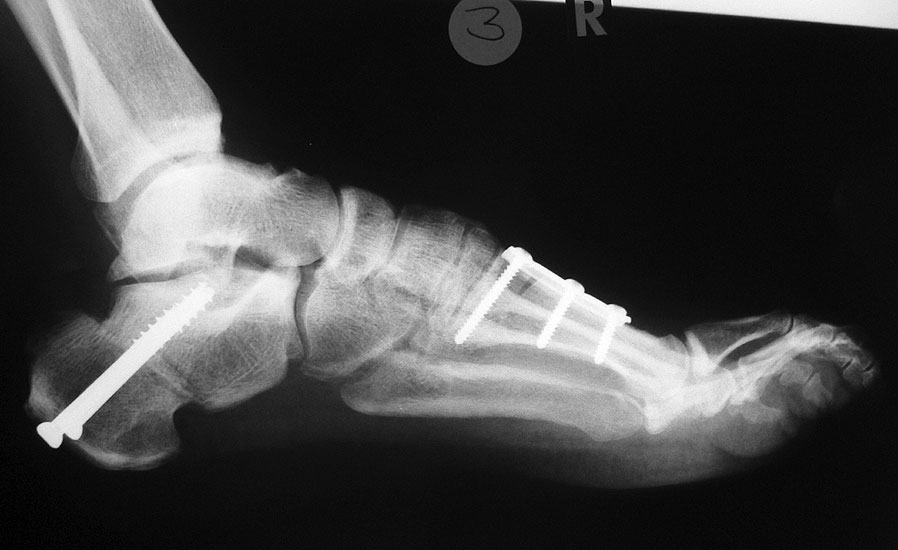

Nach einer traumatischen Ruptur der Tibials anterior Sehne kann der gleiche pathologische Mechanismus beobachtet werden (Abb. 21, 22).

Zum Lesen der Bildbeschreibung und zur Vollansicht bitte die Bilder anklicken. Bilder: A. Simon